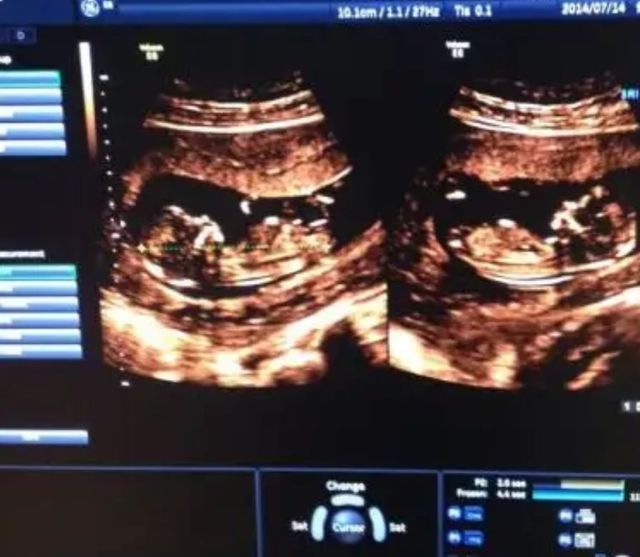

王主任:拿好仪器,涂好凝胶,放在你的小腹上,爸爸妈妈可以看你们面前的显示屏!

王主任:指了指中间,这个就是你们的小宝宝了

苏酒酒看着屏幕上刚刚有一点雏形的孩子

李洙赫拿出手里拍下小宝的图片

王主任:目前来看前三个月的风险期全是安稳度过了NT检测,孩子发育在风险值之内,接下来你可以正常的生活了,不用再卧床小心翼翼的了,我一会给你开一些孕期的保健品